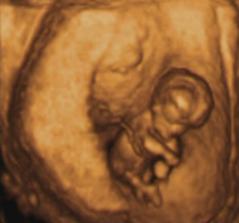

Moj prvy pokladik